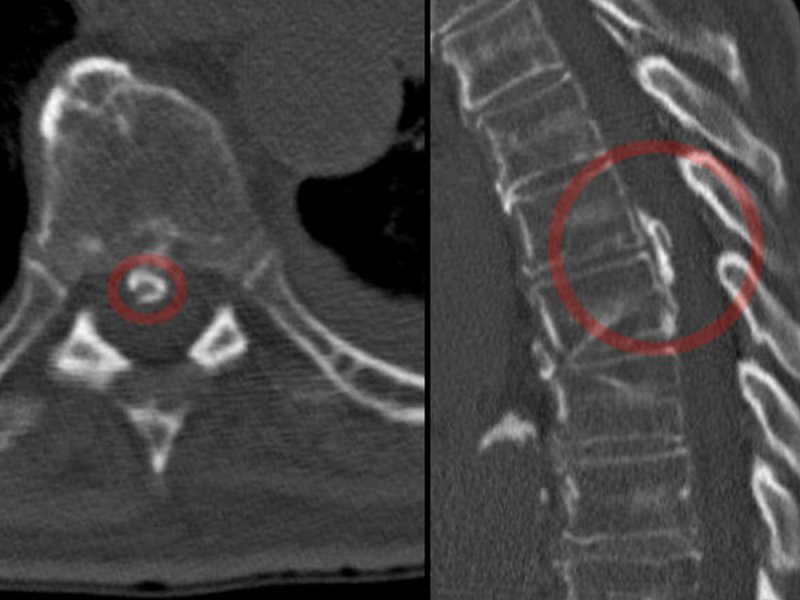

Специалисты из Корнеллского университета предложили новый двухэтапный метод восстановления после грыжи. Для этого используется гиалуроновая кислота в виде геля, которой повторно накачивается межпозвоночный диск, а с помощью коллагенового геля герметизируется отверстие, образовавшееся во время изначального разрыва.

Повреждение оболочки диска приводит к вытеканию желеобразного материала, что вызывает воспаление и боль. На данный момент кроме консервативного лечения можно выполнить сшивание разрыва без заполнения диска или наполнить его, но не предотвратить дальнейшую утечку. Новый подход решает проблемы обоих способов.